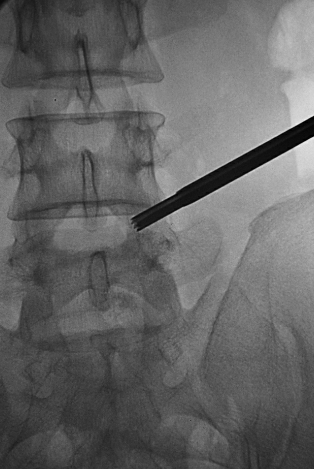

置入2级导杆使头端到达第一靶点(图18)。

图18 置入2级导杆A.前后位透视:头端到达第一靶点;B.侧位透视:侧位透头端抵达L5椎体后上缘。

拔出导丝,将导杆尾端压向腹侧,用手锤敲打导杆尾端,使导杆头端在L5椎体后缘潜行到达第二靶点(图19)。

图19 拔出导丝,将导杆尾端压向腹侧,用手锤敲打导杆尾端,使导杆头端在L5椎体后缘潜行到达第二靶点A.侧位透视头端抵达L5椎体后缘;B.前后位透视头端到达第二靶点。